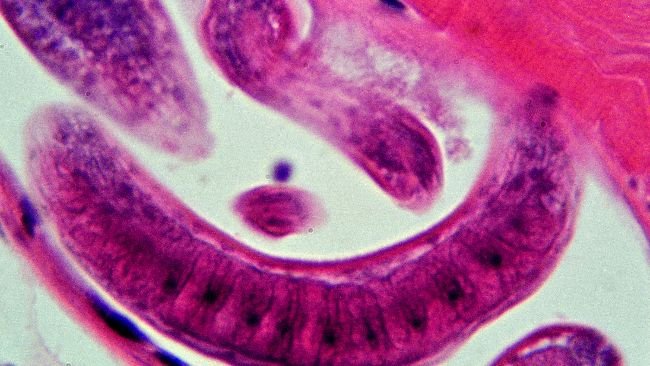

Una investigación del USDA documenta la ausencia de infección por Trichinella en cerdos comerciales.

El Senasa ha publicado un informe que ayuda a conocer mejor la distribución de esta enfermedad parasitaria causada por las larvas de Trichinella spp.